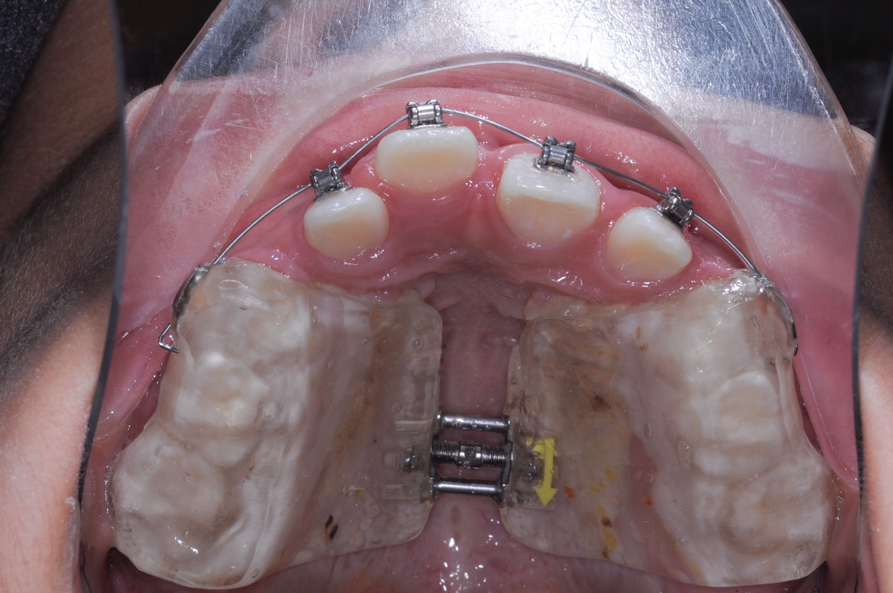

The maxillary right permanent centralincisor had a delayed eruption of 1½ years compared to its homologous incisor, and it was anteriorly displaced due to insufficient space in the premaxilla. Removal of the maxillary deciduous canines was indicated to unravel the crowding. An apically positioned flap of the impacted right central incisor was made to facilitate its eruption (Figure 5 and Figure 6). The case was worked up to plan an active phase l treatment, consisting of palatal expansion and the use of sectional fixed appliances in the upper arch. A transverse deficiency without posterior crossbite was identified, and therefore palatal expansion with a bonded expander was planned to widen the premaxilla (Figure 7 and Figure 8). A two-by-four fixed appliance system (brackets in the four maxillary anterior teeth and bands on the maxillary first molars) was used to align the maxillary teeth. The gingival margin of the retained maxillary right central incisor was slightly more apical than the left one, which erupted as expected (Figure 9 and Figure 10). Figure 11 shows a panoramic radiograph taken after completion of phase 1 treatment.

In reviewing this case more closely, the sequence usually starts with a space opening (Figure 12 through Figure 14). Palatal expansion is generally performed even without the presence of a posterior dental crossbite, as many patients with impacted maxillary central incisors are deficient in the development of the anterior portion of the maxilla.7,11 The use of sliding mechanics with open coils in conjunction with simple fixed systems is preferred to removable appliances since they deliver a light, continued force instead of an intermittent force.7 Interarch mechanics allow space to be gained for either the natural eruption or the surgical/orthodontic traction of the impacted maxillary central incisor.7 After palatal expansion, rigid structures, such as fixed transpalatal arches soldered to upper first molar bands, might first be used to anchor the active traction of the impacted tooth. Later, orthodontic fixed appliances reportedly have been used in the maxillary anterior to detail the position of the maxillary central incisor in the arch.11 Frequently, power arms are incorporated into palatal expanders.12 Fixed systems initially employ flexible nitinol wires and round stainless-steel wires. After initial leveling, rectangular stainless-steel wires have been used as part of several protocols to produce torque and place the roots of the resolved impacted central incisor in the proper position in its apical base.3,7,13 Orthodontic traction is conducted with different systems based on the preference of the clinician.3,7,10

Fig 12. After expansion of the maxillary arch, the modified palatal expander was used for traction of the impacted maxillary right central incisor. Fig 12: Palatal expansion to gain space in the premaxilla for the impacted maxillary right central incisor. Fig 13: Traction of the impacted maxillary right central incisor through a palatal orthodontic attachment and the use of a power arm incorporated in the expander. Fig 14: Detailing the position of the impacted maxillary right central incisor with orthodontic fixed appliances.

Fig 13. After expansion of the maxillary arch, the modified palatal expander was used for traction of the impacted maxillary right central incisor. Fig 12: Palatal expansion to gain space in the premaxilla for the impacted maxillary right central incisor. Fig 13: Traction of the impacted maxillary right central incisor through a palatal orthodontic attachment and the use of a power arm incorporated in the expander. Fig 14: Detailing the position of the impacted maxillary right central incisor with orthodontic fixed appliances.

Fig 14. After expansion of the maxillary arch, the modified palatal expander was used for traction of the impacted maxillary right central incisor. Fig 12: Palatal expansion to gain space in the premaxilla for the impacted maxillary right central incisor. Fig 13: Traction of the impacted maxillary right central incisor through a palatal orthodontic attachment and the use of a power arm incorporated in the expander. Fig 14: Detailing the position of the impacted maxillary right central incisor with orthodontic fixed appliances.

Figure 14